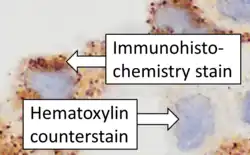

Counterstains

After immunohistochemical staining of the target antigen, another stain is often applied. The counterstain provide contrast that helps the primary stain stand out and makes it easier to examine the tissue morphology. It also helps with orientation and visualization of the tissue section. Hematoxylin is commonly used.[6][15]